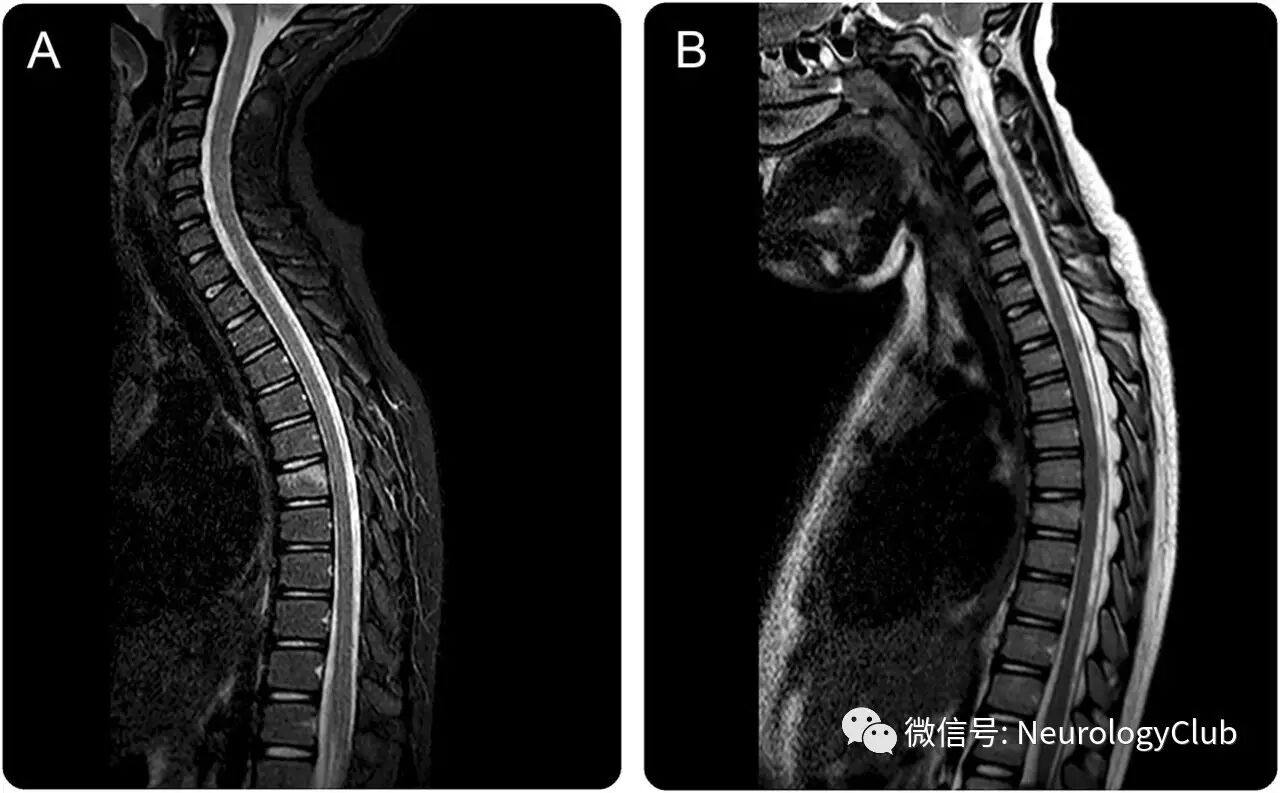

(图:A:背部外伤后的脊髓MRI提示T7椎体楔状骨折伴水肿,未见脊髓实质病灶;B:背部外伤1月后复查脊髓MRI提示T7椎体水肿消失)